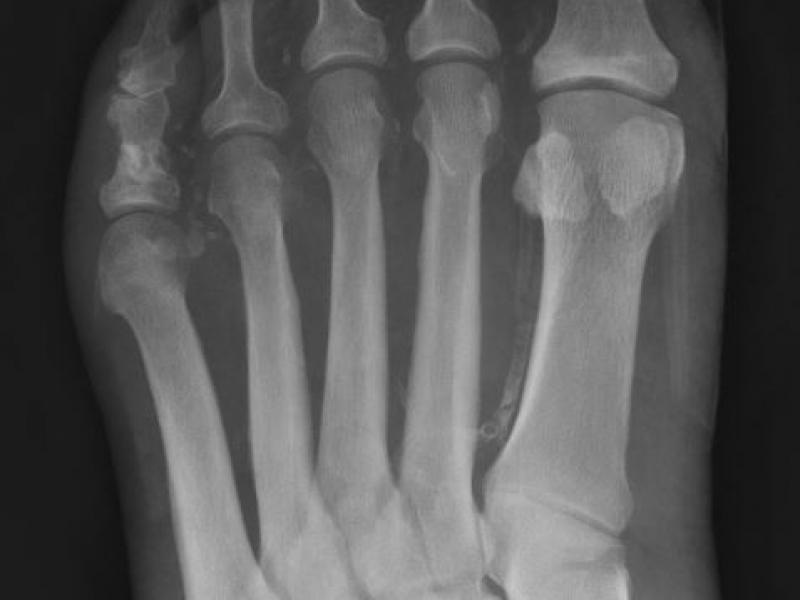

A 65 yo male pmhx DM, HTN, HLD, presents with left foot pain